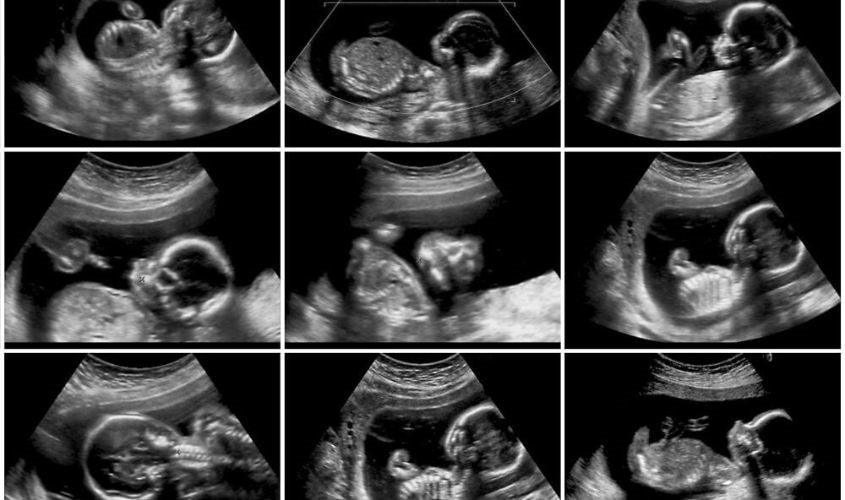

Ở tuần thứ 20 thai nhi có sự phát triển vượt bậc, mặc dù bộ phận sinh dục bên ngoài vẫn đang hình thành nhưng mẹ vẫn có thể biết được giới tính của bé thông qua kết quả siêu âm ở tuần thứ 18 đến 22.

• Ở tuần thứ 20, siêu âm sẽ giúp mẹ biết được sự phát triển của thai nhi dù các cơ quan của thai nhi vẫn trong quá trình hình thành từ dòng chảy của tim – tĩnh mạch chủ, động mạch chủ và động mạch phổi.

• Siêu âm thai ở tuần thứ 22 bác sĩ sẽ xác định được sự phát triển hình thái của thai nhi, tình trạng thai và phát hiện dị tật, bất thường (nếu có). Chính vì thế đây là cột mốc siêu âm cực kỳ quan trọng mà các mẹ không thể bỏ qua.